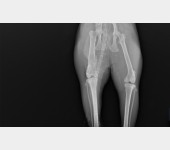

Trzy lata temu odłowiłam na osiedlu do sterylizacji dziką około 2letnią kotkę, która nazwaliśmy LUSI. Okazało się, że ma gorączkę, zapalenie płuc i inne przypadłości kota dziko - żyjącego. Z uwagi na konieczność leczenia, LUSIA zamieszkała z nami. Bardzo szybko zaadoptowała się do nowych warunków, więc została z nami. W tym roku zrealizowałam moje marzenie i przeprowadziłam się do mieszkania z ogródkiem. W trakcie prac wykończeniowych, przez nieuwagę pracownika wystraszona uciekła. Blisko 3 miesiące poszukiwałam ją bezskutecznie, aż do 18 marca Tego dnia szłam do domu i kotka słysząc mój głos, wyczołgała się z krzaków pod moje nogi ciągnąc za sobą tylną łapkę. Od razu udałam się do weterynarza i cios w serce... Okazało się, że LUSI została brutalnie, z wielką siłą potrącona przez samochód kilka tygodni wcześniej i pozostawiona w olbrzymim bólu i cierpieniu. Kotka po tym zdarzeniu zdziczała, ale nie dając za wygraną udałam się do znanego i polecanego specjalisty chirurga – ortopedy. Weterynarz zaleciła dalszą diagnostykę neurologiczną, leczenie farmakologiczne i dała nadzieję na wyzdrowienie kotki po zoperowaniu jej pękniętej miednicy i łapki. Niestety z uwagi na trudną sytuację finansową, nie jestem w stanie sama podołać tym kosztom. Bardzo proszę o wsparcie, abym mogła ulżyć kotce w cierpieniu.